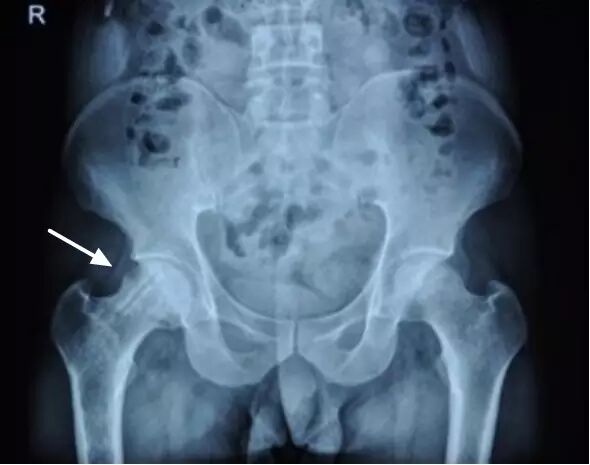

II期病人有髋部症状,磁共振出现异常,X线片显示股骨头出现透光和硬化改变

II期和III期的患者治疗方法相同,因为此时股骨头虽然还没有变形,暂时还不需要行人工关节置换术,但是股骨头已经出现空洞,随时股骨头就会塌陷变形,所以单纯的股骨头减压术是不能达到治疗效果的。这时就需要在股骨头减压的同时,植入一根支撑棒,顶住股骨头空洞区,防止股骨头在负重的情况下过早塌陷。其他治疗同之前相同,口服以上药物,定期复查,密切观察病情发展,尽量避免重体力劳动和爬山爬楼。

以上为股骨头坏死减压加支撑棒植入术示意图和术后X线片